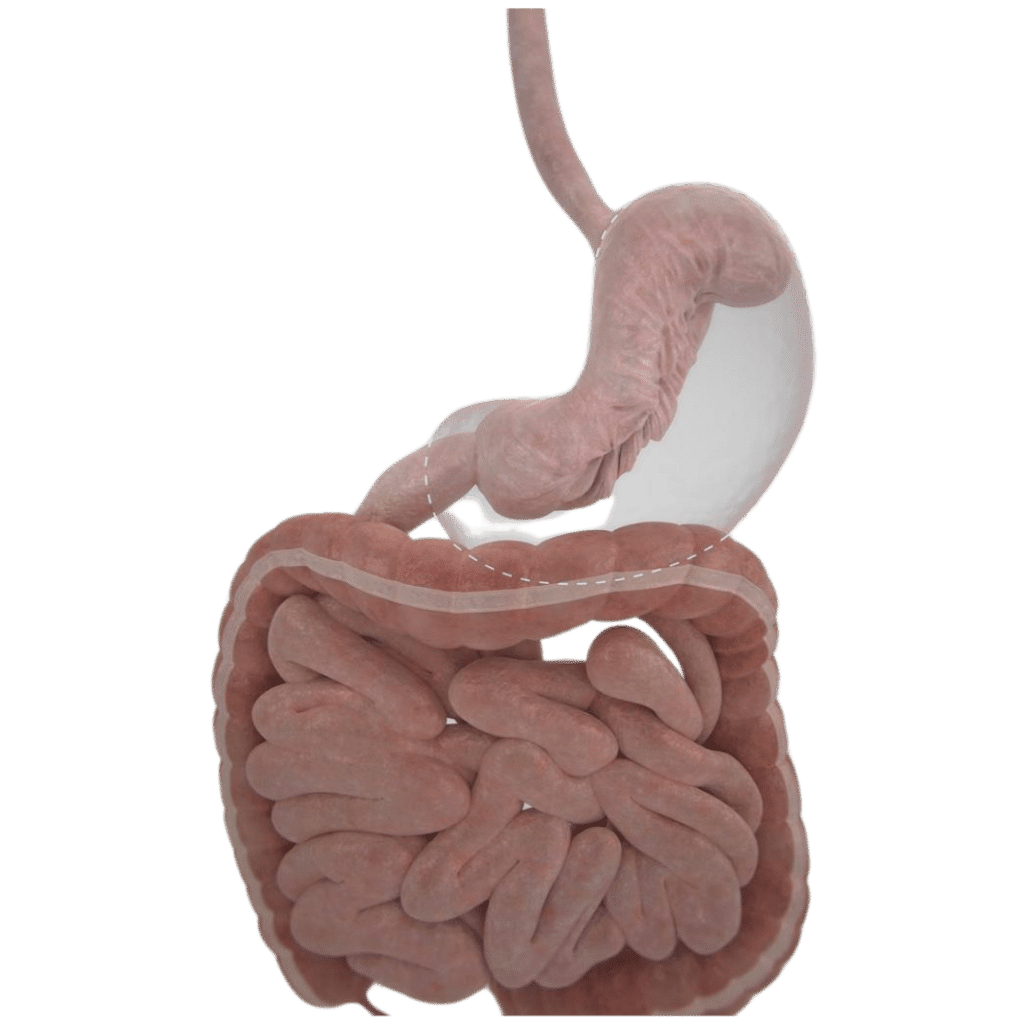

La manga gástrica endoscópica es un procedimiento bariátrico de manga gástrica que se realiza sin cirugía.

Utilizamos un endoscopio especializado (Apollo) que nos permite “coser” el estómago por dentro y achicarlo hasta en un 80% de su tamaño sin la necesidad de recortarlo.

Es decir, reducimos su capacidad significativamente, de esta manera el paciente tiene menos hambre y se satisface rápidamente luego de cada comida, favoreciendo así el descenso de peso.